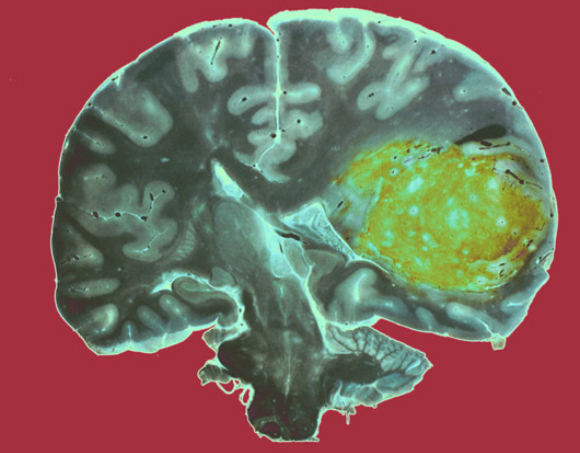

גידולי מוח רבים עדיין חשוכי מרפא. גידול גליובלסטומה (ירוק) באונה הרקתית של אדם | צילום: CNRI / SCIENCE PHOTO LIBRARY